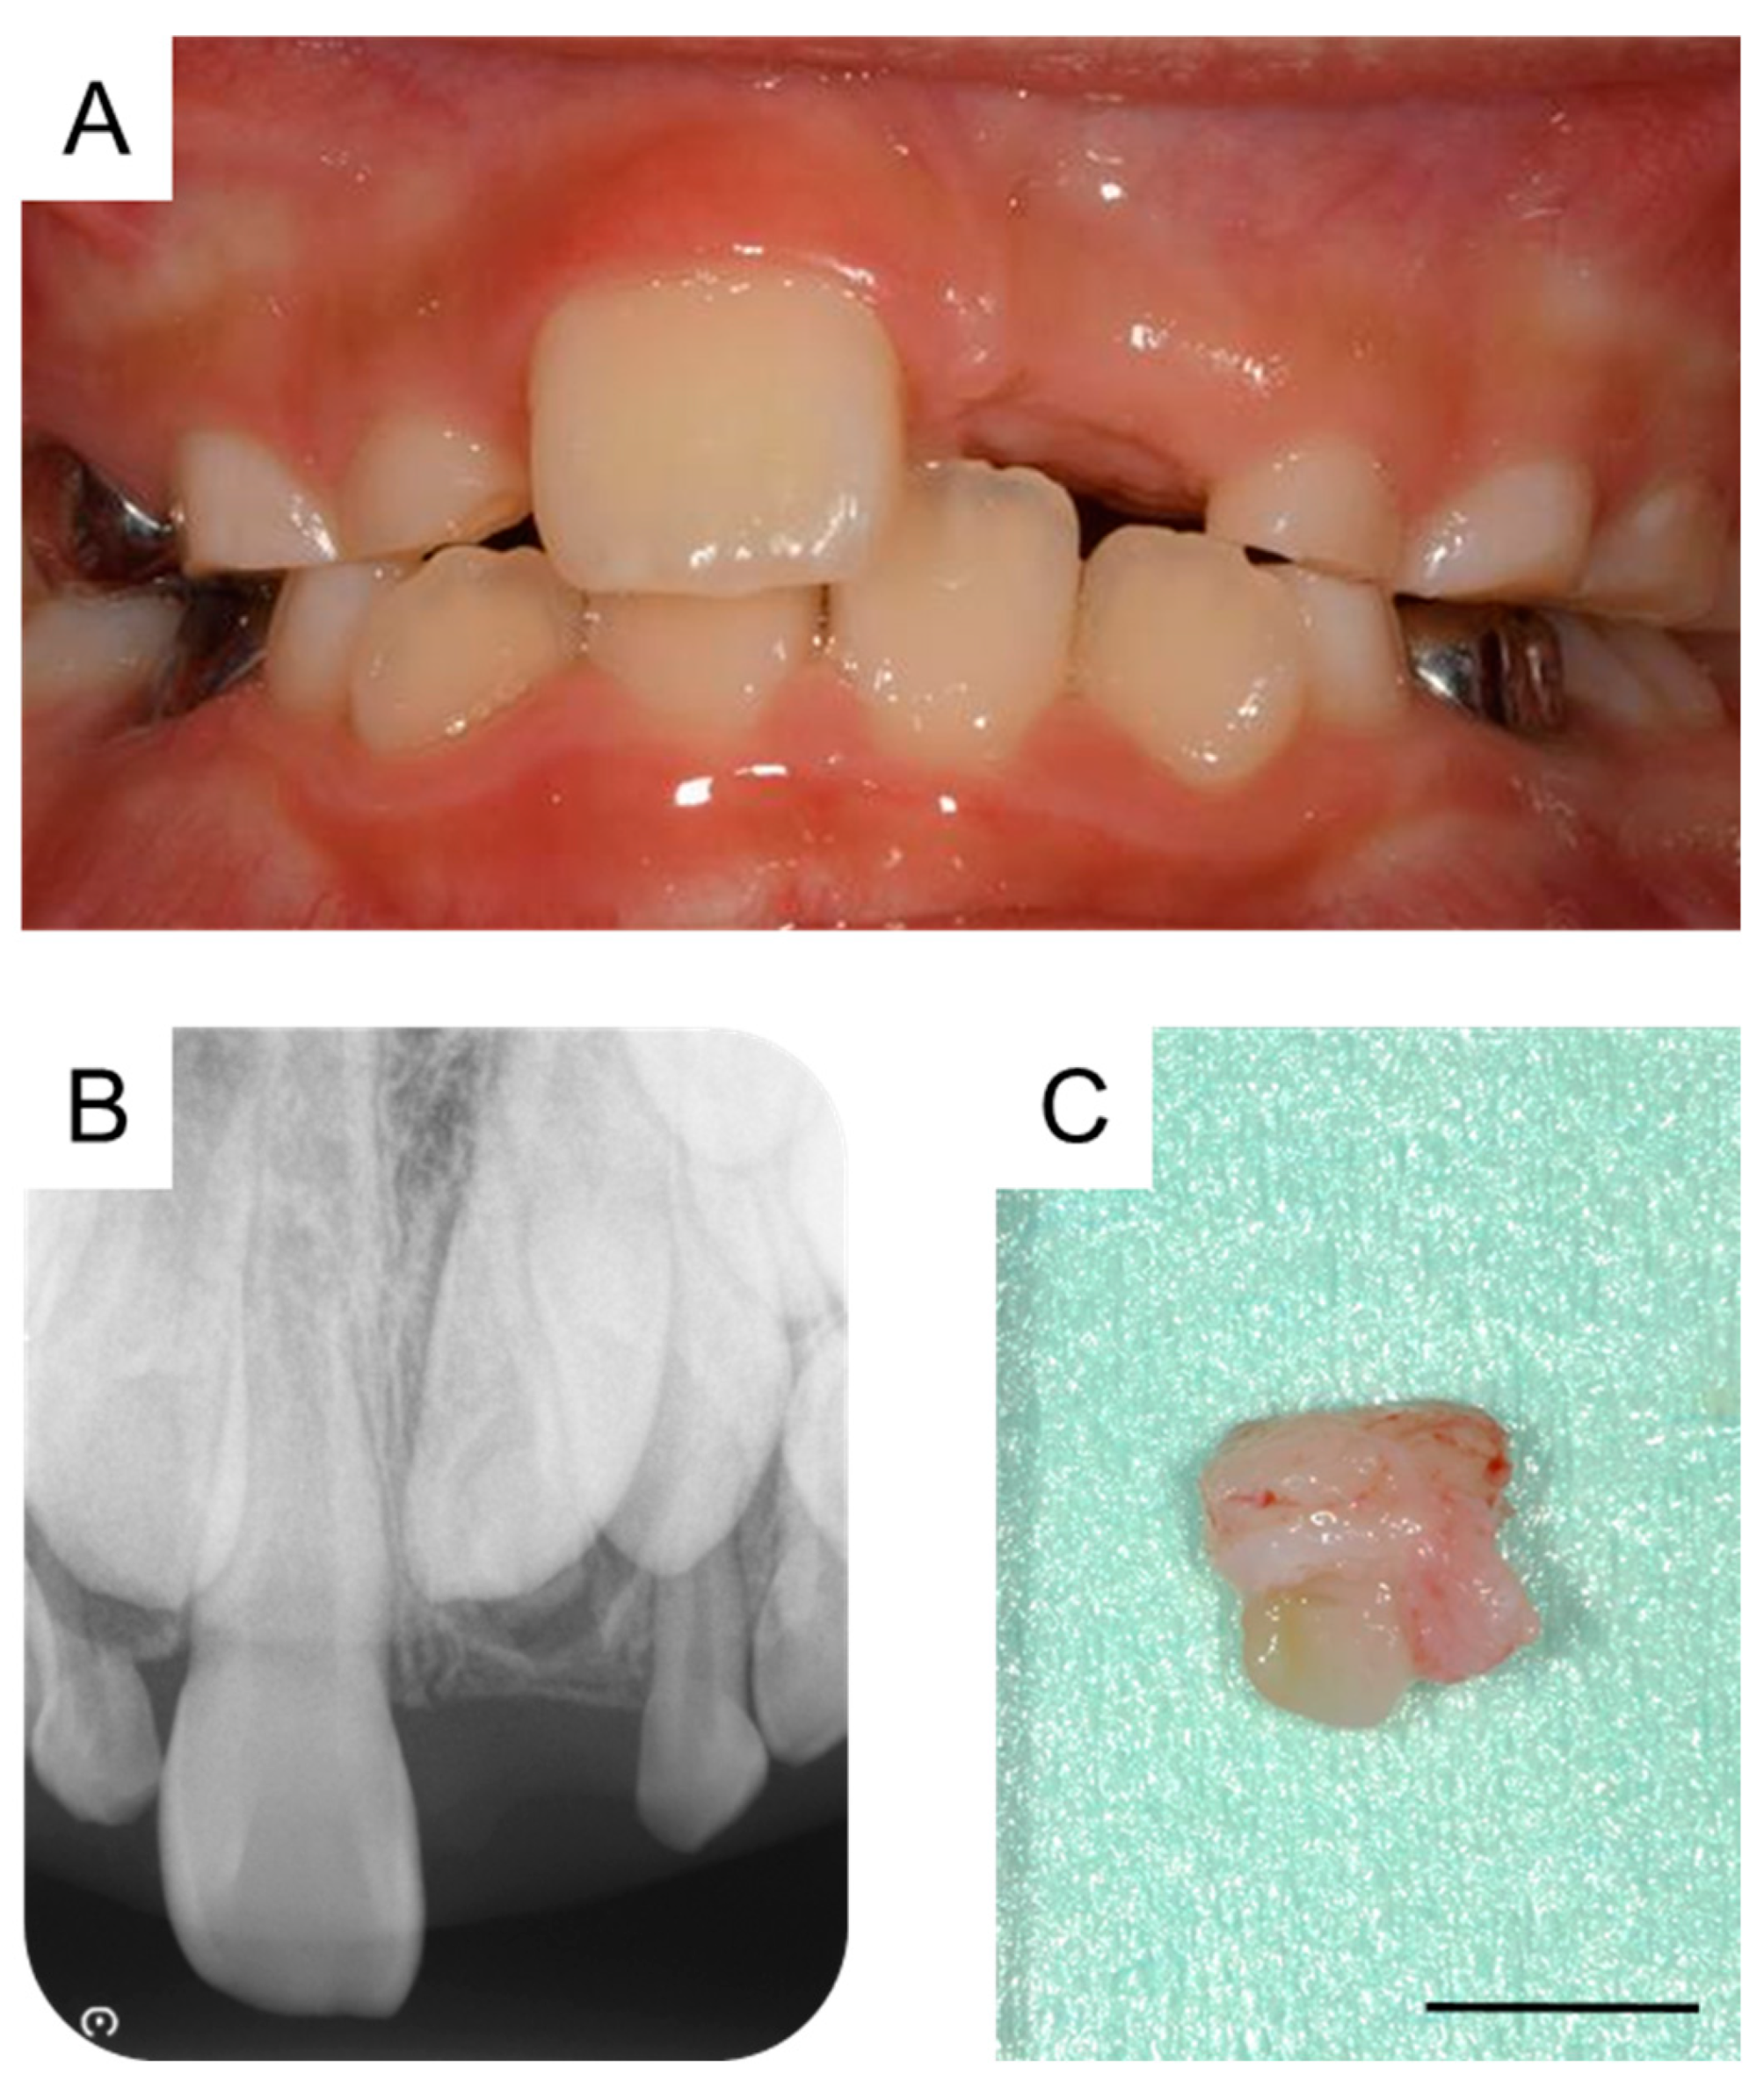

A small radiolucency was observed near the crown of the maxillary left central incisor in the dental X-ray image taken during the first extraction. The dental X-ray images at 6 years and 3 months and 7 years and 5 months showed a progressive growth of this structure (Figure 2A,B), which was subsequently diagnosed as a supernumerary tooth (second supernumerary tooth). We extracted the second supernumerary tooth at 7 years and 7 months (Figure 2C). According to the general surgical procedure, debridement and suturing were performed. Radiographic examination at the age of 7 years and 9 months revealed an absence of any calcified tissue. However, a radiolucent image was observed around the germ of the permanent maxillary left central incisor (Figure 2D). Details of the first and second supernumerary teeth have been described in the previous report [5].

Dentistry 11 00049 g001

Figure 2. Extraction of the second supernumerary tooth. (A) Periapical radiograph after the extraction of the first supernumerary tooth at the age of 6 years and 3 months. (B) Periapical radiograph of the second supernumerary tooth detected at the age of 7 years and 5 months. (C) Extracted second supernumerary tooth at the age of 7 years and 7 months. Scale bar: 5 mm. (D) Periapical radiograph after the extraction of the second supernumerary tooth at the age of 7 years and 9 months.